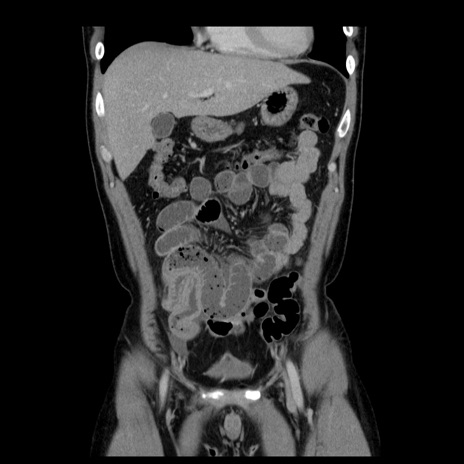

症例4(冠状断像)

【症例】30歳代男性

【主訴】腹痛、嘔吐

【現病歴】昨晩から突然の腹痛あり、その後嘔吐、軟便も出現。腹痛が改善しないため救急搬送となる。2日前にしめ鯖の食事歴あり。

【身体所見】意識清明、苦悶様、BP 135/90mmHg、BT 35.7℃、腹部:平坦、やや硬、心窩部〜臍部に自発痛、圧痛あり、筋性防御+、反跳痛-

【データ】WBC 8100、CRP 0.57